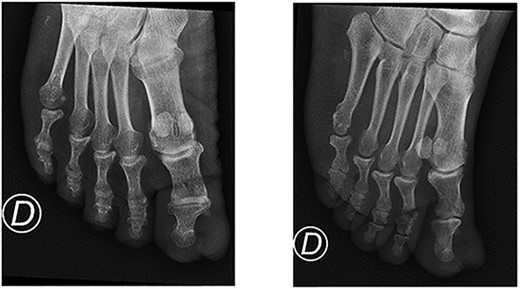

The wound was left open for secondary healing and the patient received careful wound care. At the 6-month follow-up, the patient did not complain of any aesthetic or functional issues or pain and there was no evidence of local recurrence (Figs 7 and 8).